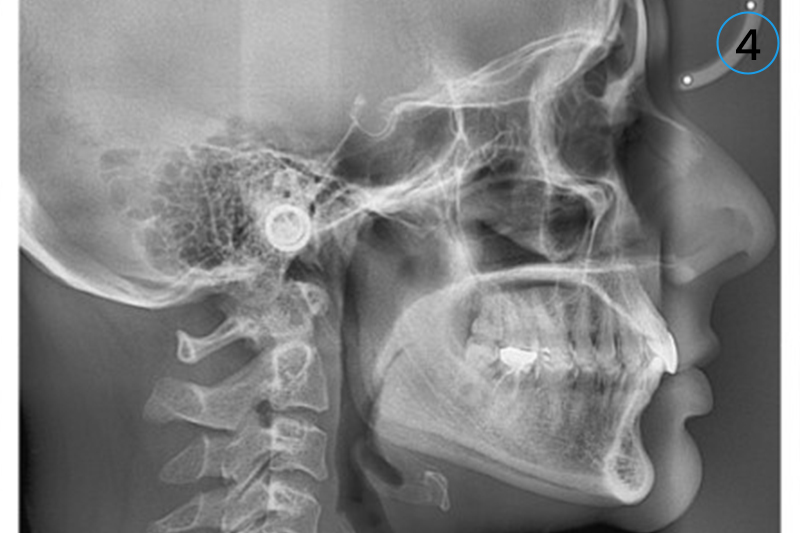

• 4. Lateral Cephalogram (Digital Format)